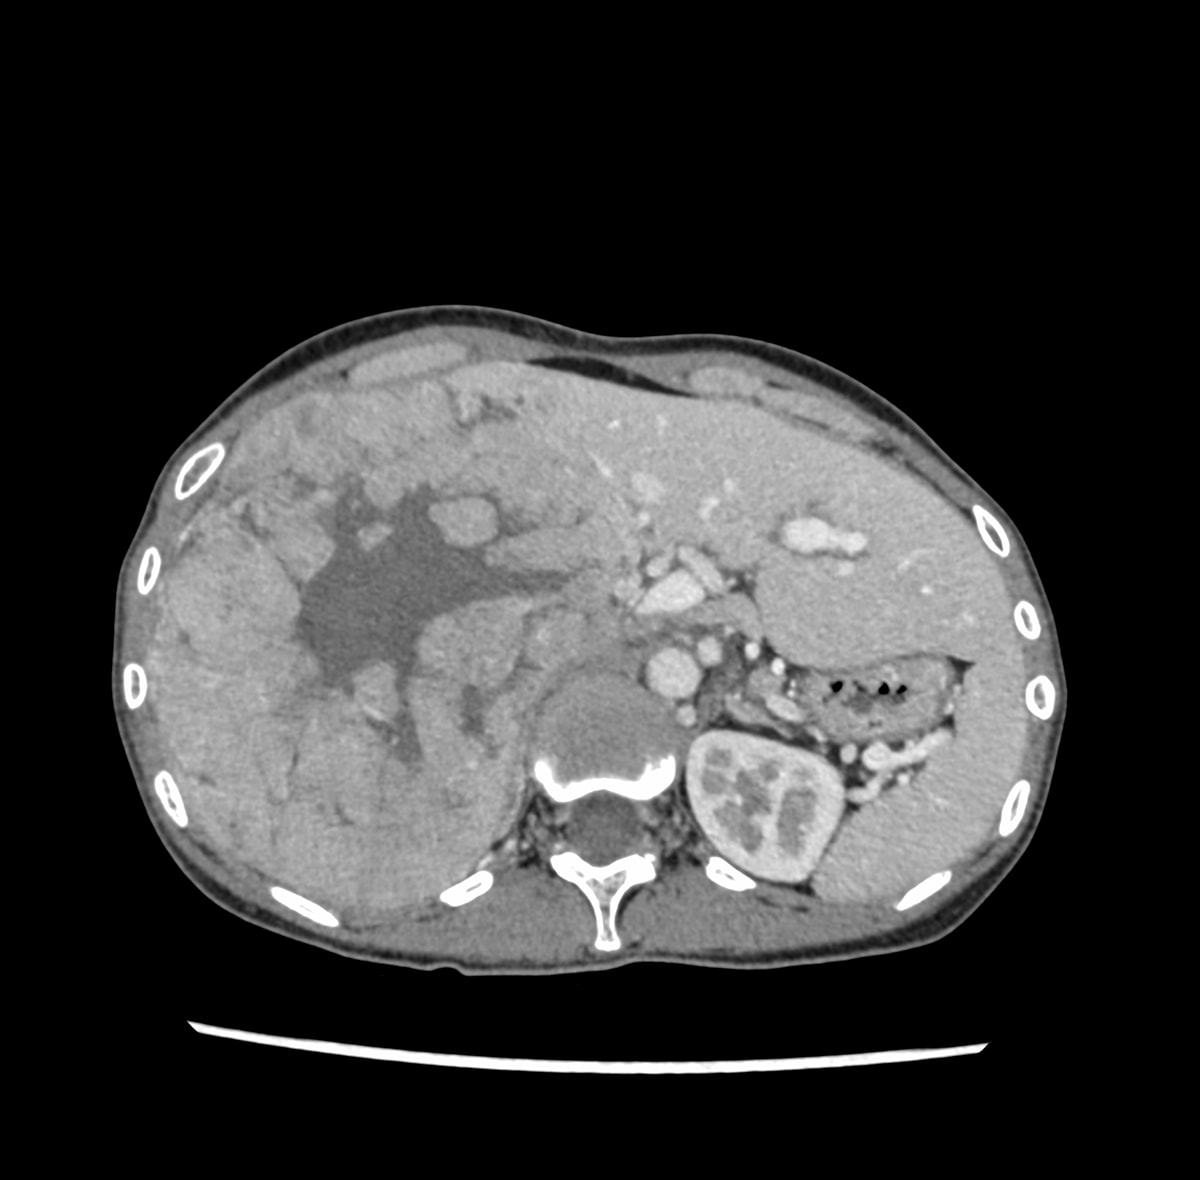

30歳代、女性、38kg、肝細胞癌

右上腹部違和感にて他院を受診し,CTで肝右葉を首座とする巨大肝腫瘍を認め,精査目的に当院紹介.

肝右葉を首座とする24cm大の多結節癒合状の腫瘤性病変を認める.単純CTでは肝実質と等吸収を示し,内部に低吸収域や石灰化を伴っている.造影後早期動脈相から後期動脈相にかけて結節間でやや不均一な早期造影効果を認め,肝静脈相以降では肝実質より相対的に低吸収を示す.門脈本幹から一次分枝レベルにて明らかな造影欠損を認めない.肝細胞癌が疑われ外科的切除が施行され,高~中分化型肝細胞癌と診断された.